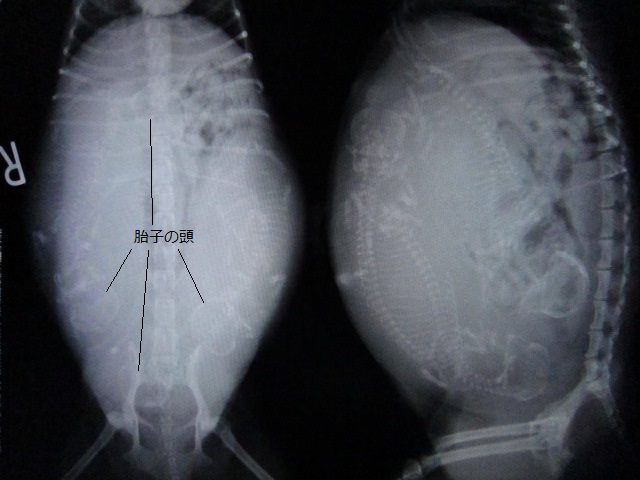

術前のレントゲンです。

4頭の胎子がいます。